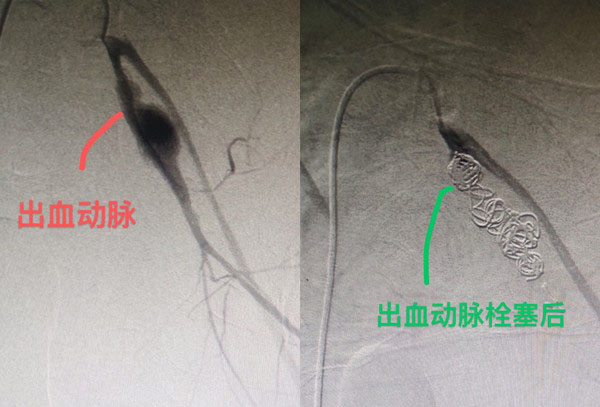

男子患髂動脈瘤破裂大量失血

在進行超聲波檢查期間,趙先生突然暈倒,醫生懷疑為「髂動脈瘤破裂」,於是緊急將他轉送至湖南省人民醫院天心閣院區,當時趙先生已失去意識、兩眼反白、每分鐘心跳率高達140次、血壓降至休克狀態,而且破裂的髂動脈如「打開的水龍頭」不斷冒出鮮血,瀕臨人體失血的極限差點喪命。

幸好,在醫療團隊搶救下,趙先生僅接受了一個多小時的手術,在大量輸血後撿回一命。醫生透露,團隊在搶救過程中輸血量達人體總血量的70%血量,據指人體若失去總血量的20%就會休克,如達到30%又未能及時搶救,患者就會在短時間內死亡。